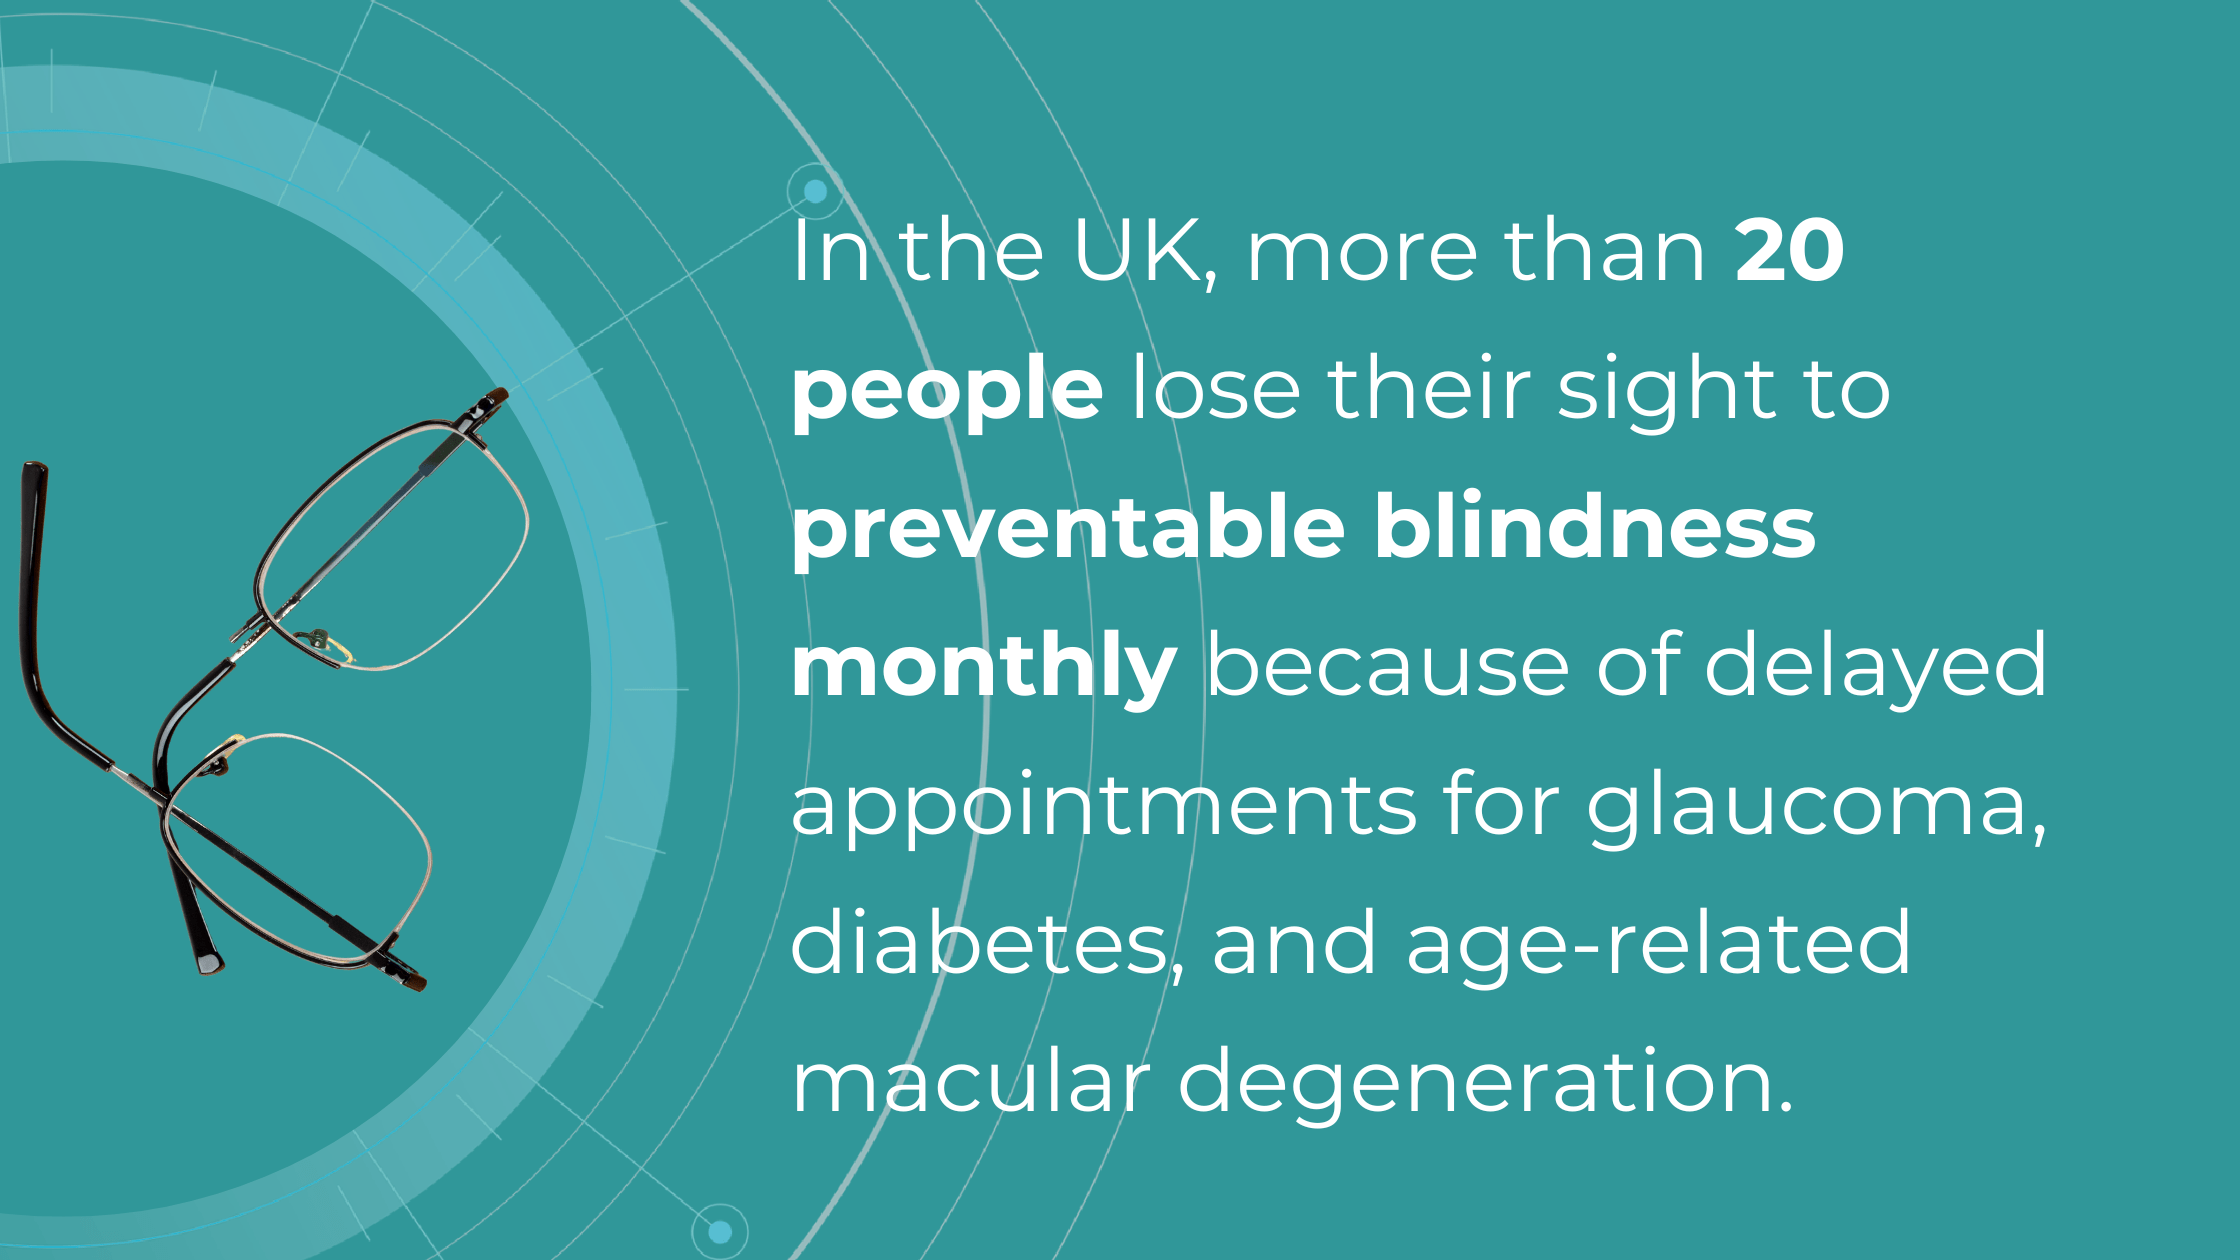

The National Health Service (NHS) is grappling with significant backlogs in ophthalmology services, which account for nearly 10% of the 7.8 million patients awaiting treatment.

The consistently high average number of patients waiting per trust in Ophthalmology, with high follow-up waitlists, delays care that poses substantial risks. The Royal College of Ophthalmologists reported that the risk of permanent visual loss is nine times higher in follow-up patients than in new patients. With 30% more patients on ophthalmology waitlists than pre-pandemic, the number of people at risk of sight loss may have increased.

Community Eyecare (CHEC), a provider of community-based ophthalmology services, received around 1000 referrals per week before the pandemic, further highlighting the strain on the system.